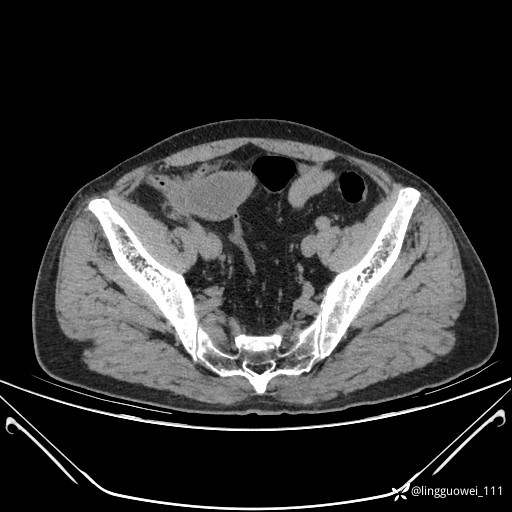

62岁,男,2天前无明显诱因出现下腹部疼痛不适,呈持续性,程度稍剧,同时伴有尿频、尿急及尿不尽感,无畏寒、发热。

平扫: